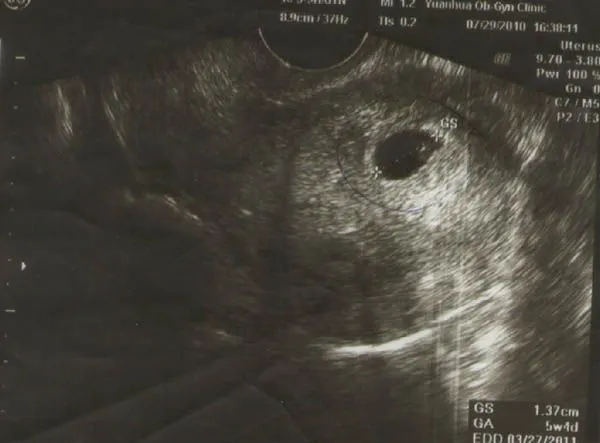

知道懷孕的消息一點都沒有開心的感覺其實是震撼....超級震撼━Σ(゚Д゚|||)━